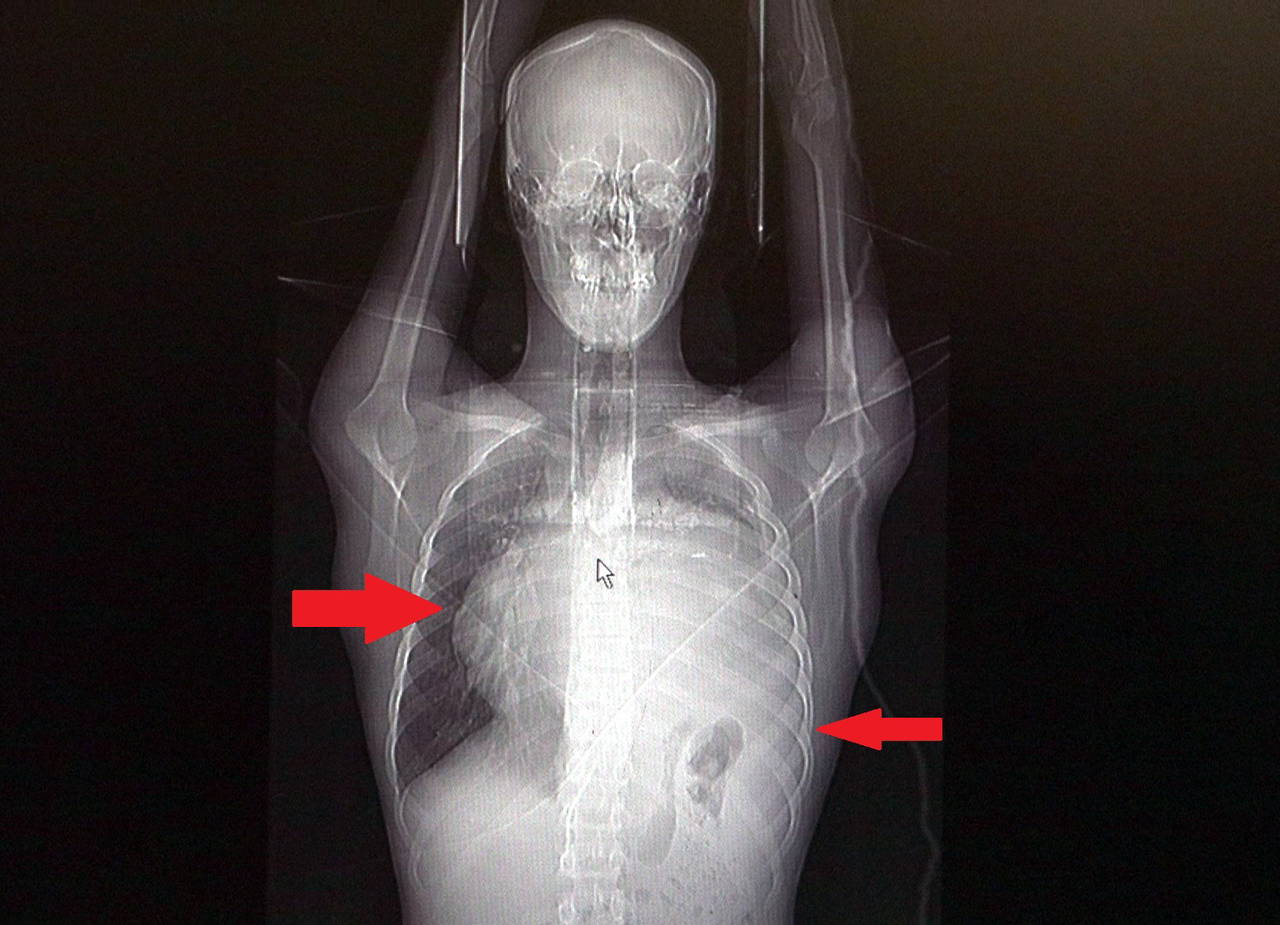

Kitleyi küçültmek için kemoterapi uygulansa da tam tersine tümör 2 ay içinde neredeyse 10 katına çıktı ve büyük bir karpuz boyutuna ulaştı. Sol akciğerinin yüzde seksenini kağıt gibi ezen, kalbini göğüs duvarında 12 santim sağa kaydıran ve hem kalbe hem beyne giden ana damarlara baskı yapan 6.5 kilo ağırlığındaki dev tümör, Göğüs ve Kalp Damar Cerrahisi ekiplerinin birlikte girdiği operasyonla başarılı şekilde çıkarıldı.

Operasyon sırasında Aktaş’ın kalbi normal yerine çekildi, sol akciğerin üst lobu alındı, ezilen alt lobu ise anestezi ekipleri tarafından pozitif basınçla yeniden şişirildi. Ameliyatı gerçekleştiren ekipten Prof. Dr. Erdal Taşçı, Aktaş’ın göğüs boşluğunun neredeyse tamamını kaplayan 6,5 kiloluk tümörün teratom (eski Yunancada ‘canavar tümör’) türlerinden biri olduğunu ve embriyonik hücrelerden kaynaklandığını kaydetti.

Prof. Dr. Erdal Taşçı, "Bundan 2,5-3 ay öncesine kadar hiçbir problemi olmayan, hayatını normal devam ettiren bir delikanlı Burak. Göğüs ağrısı öksürük ve nefes darlığı şikayetiyle sağlık kuruluşuna başvuruyor. Orada yapılan tetkiklerinde sol göğüs boşluğunda akciğerinden kaynaklanmayan portakal büyüklüğünde bir kitle tespit ediliyor ve immatür teratom tanısı konuyor. 2 ay arayla yapılan tetkiklerinde ve arada cerrahi öncesi küçültme amaçlı kemoterapi almasına rağmen, portakal büyüklüğündeki tümör, irice bir karpuz büyüklüğüne, yaklaşık 6 kilo 300 grama kadar ulaşıyor. Göğüs boşluğunda kemik kafesi içinde olduğu için, itebileceği iki organ var; biri kalp, diğeri de akciğerler. Soldan sağa doğru büyüdüğü için kalbi tamamen göğüs boşluğunun sağ tarafına itmiş ve kalbe giren ve kalpten çıkan bütün büyük damarları da yer değiştirmenin etkisiyle bükülmüş durumdaydı" diyerek açıklamlarına şu şekilde devam etti:

Normalde kalbin özellikle alt ucunun göğüs boşluğunda, iman tahtası orta çizgi kabul edilirse, sola bakar şekilde durduğuna dikkat çeken Prof. Dr. Taşçı, sözlerini şöyle sürdürdü:

"Ama bu hastada yaklaşık 12-13 s santimlik kalbin alt ucununu yer değiştirmesi ve kalbe giren çıkan bütün damarlar bükülüp kan akımı bozulmuştu. Kalp Damar Cerrahisi ekibi de bizimle beraber ameliyata girdi. Sol akciğerin üst lobu artık geri dönüşümsüz olarak ezildiği için çıkarmak zorunda kaldık. Kalbi tekrar eski pozisyonuna getirdik. Ameliyat sonrası çok çabuk toparladı. Koşuyolu ailesi olarak böyle büyük bir vakanın altından başarıyla çıktığımız için de ayrıca çok gururluyuz. Bundan sonra onkolog arkadaşlarımız hastamızın yaşamına çok olumlu dokunuşlar yapacak. İmmatür teratom genelde embriyojenik çağda gelişim gösteren germ hücrelerinin farklılaşmasıyla büyür. Vücudun herhangi bir yerinde gelişebilir ve içinde saç, diş, kemik artıkları, jölemsi kıvamda maddeler bulundurabilen bir tümör çeşididir. Kombine tedavilerde çok iyi sonuçlar alınıyor. Bu çocuğumuzu ileride güzel bir hayat bekliyor."